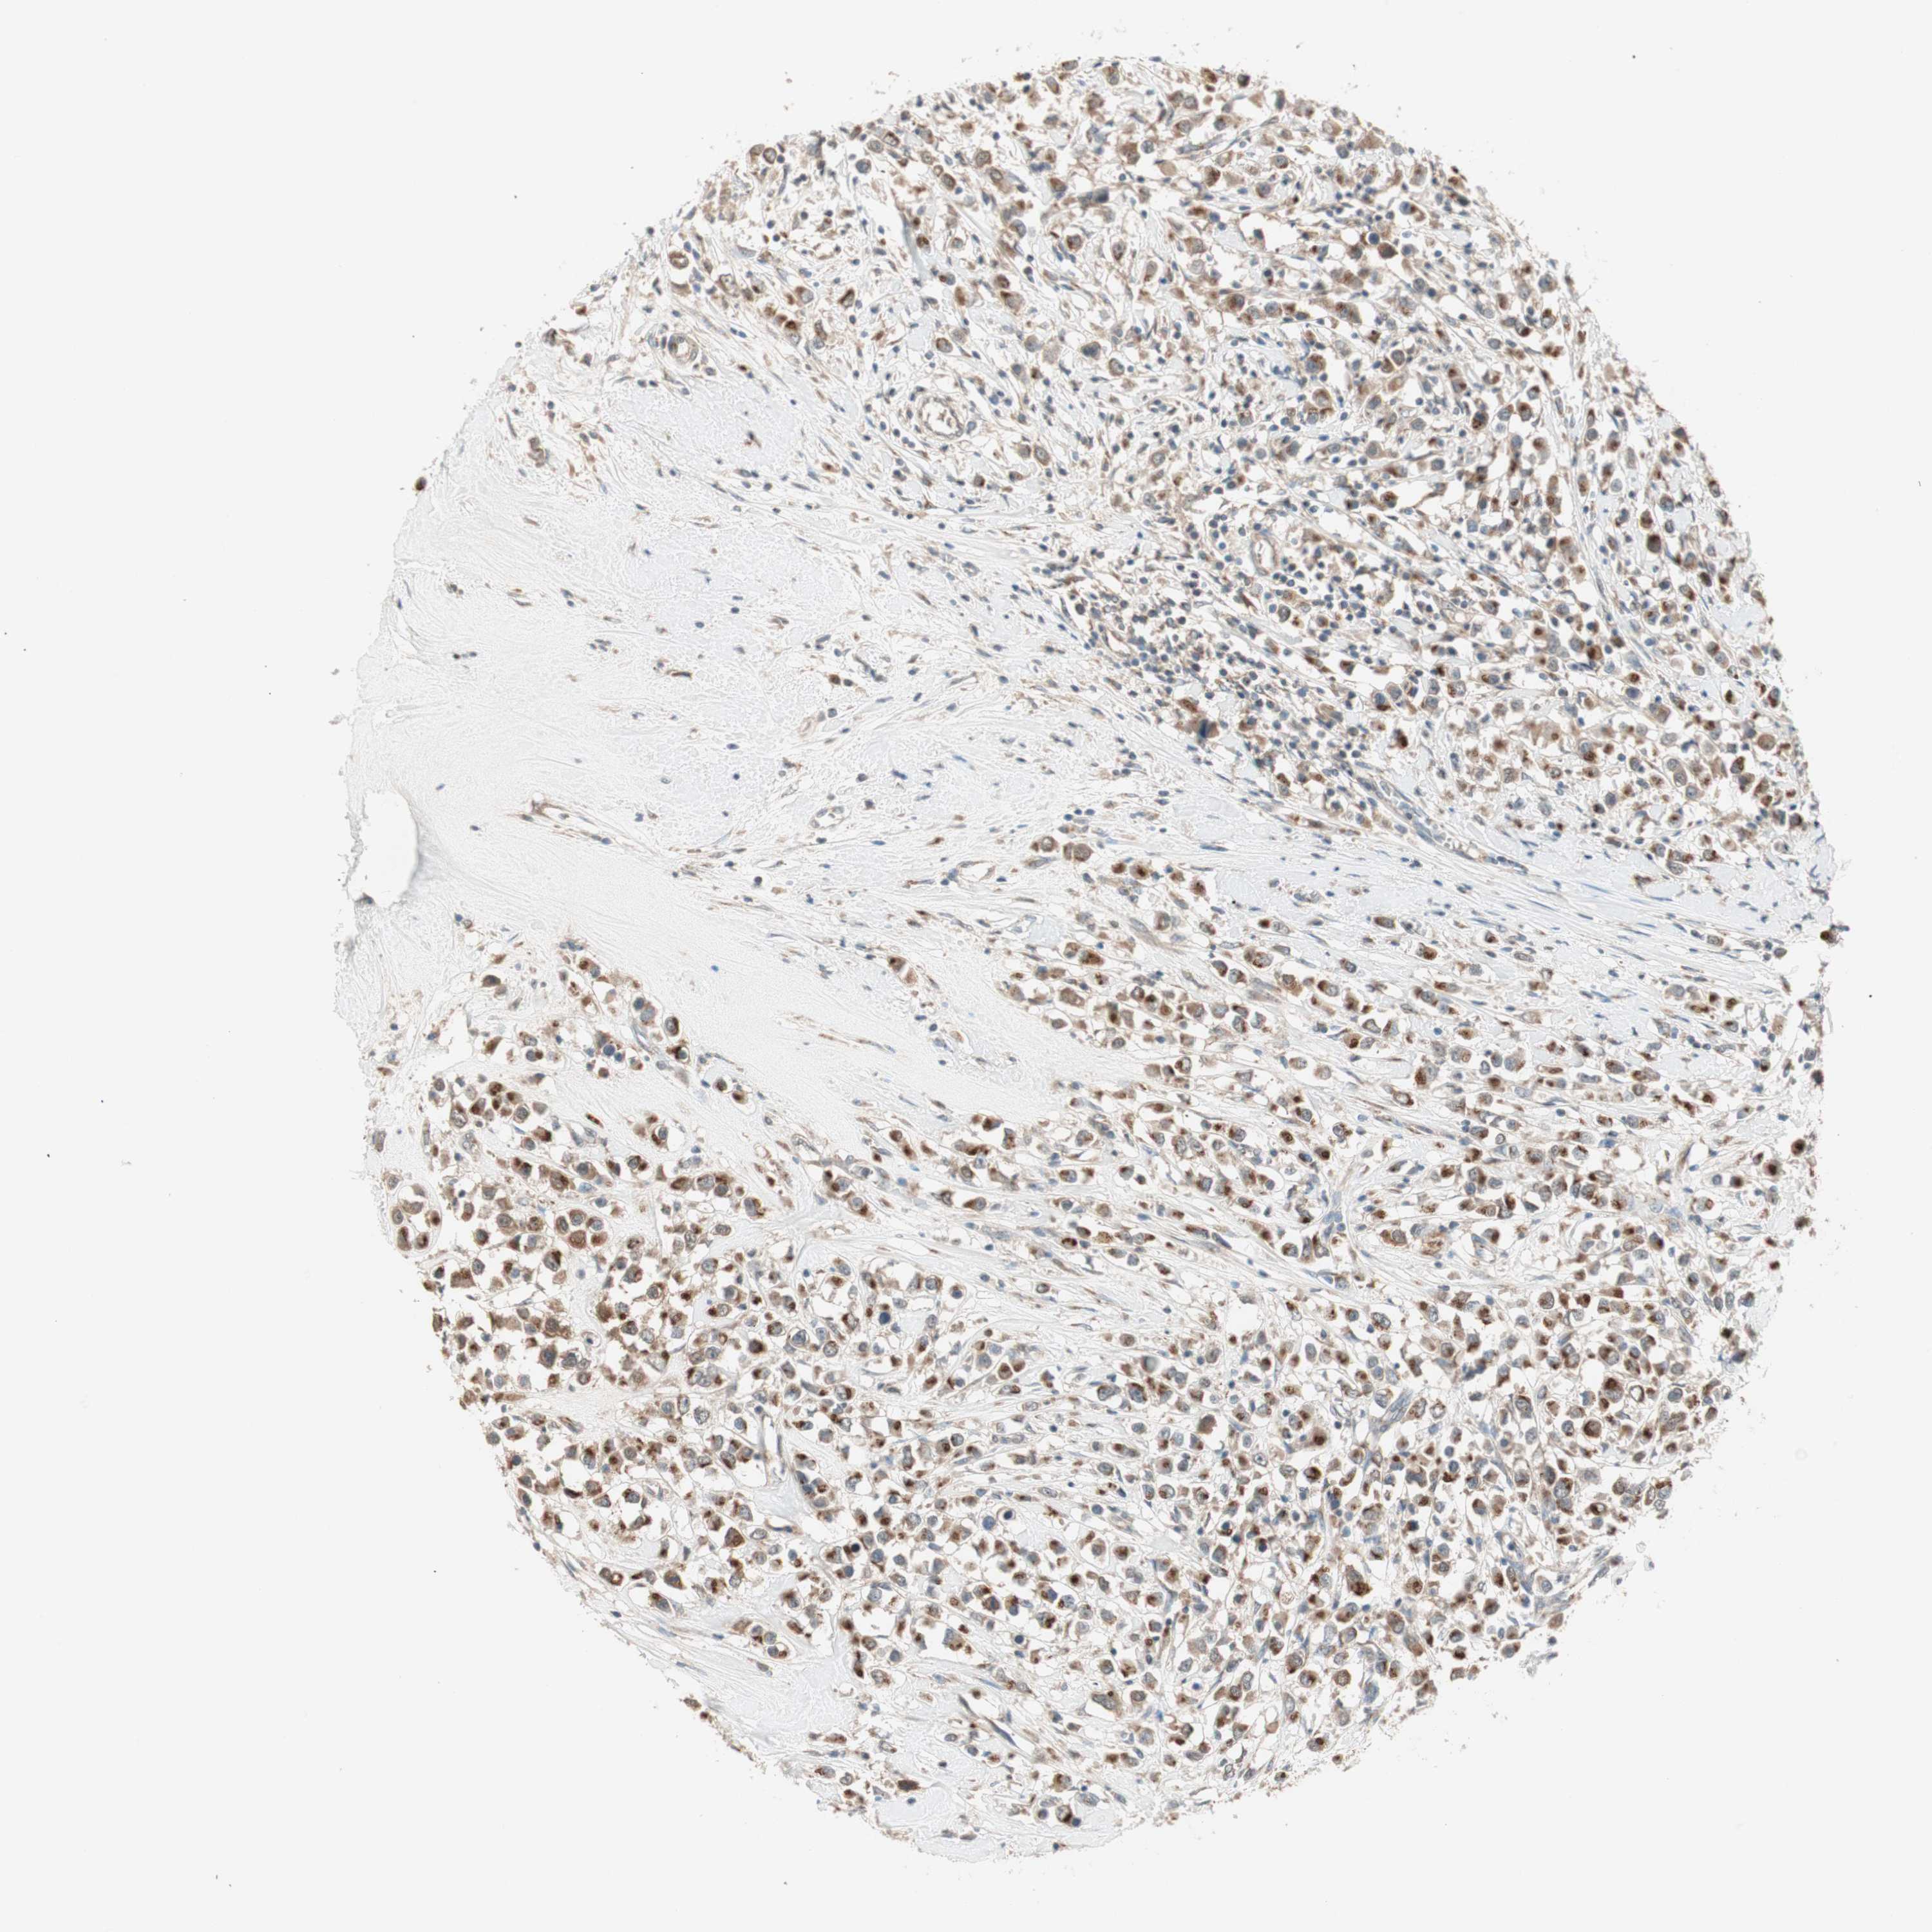

BRCA TCGA BRCA VALIDATION PROTEIN EXPRESSION

ANTIBODIES

AND

VALIDATION